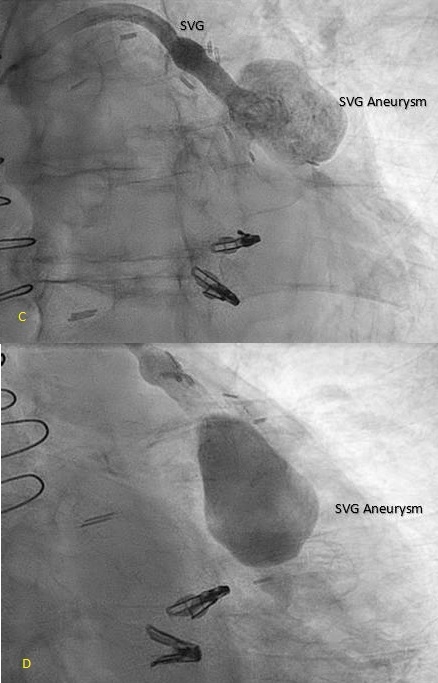

An 80-year-old patient with a history of coronary artery disease status post CABG in 2021, paroxysmal atrial fibrillation, heart failure with preserved ejection fraction, severe mitral regurgitation status post TEER-MitraClip, and moderate-to-severe aortic stenosis (aortic valve area 0.6 cm2, mean gradient 31 mmHg) presented with progressive exertional dyspnea, weakness, and lightheadedness. Transthoracic echocardiography confirmed moderate-to-severe aortic stenosis, and a cardiac CT was obtained for transcatheter aortic valve replacement (TAVR) evaluation. Imaging incidentally revealed a 3.1 cm SVG aneurysm with suspected intraluminal thrombus, prompting initiation of anticoagulation and left heart catheterization to further characterize the aneurysm.

SVG aneurysms are rare and pose a complex clinical challenge. A recent review offers proposed management strategies. Current management requires individualized treatment decisions based on patient risk, aneurysm type, size, presence of complications, whether symptomatic, and available expertise. The three current mainstays of treatment include observation and medical therapy, surgery and percutaneous intervention. Medical therapy and observation are preferred for patients that are high risk surgical candidates, or have multiple comorbidities. Percutaneous interventions are minimally invasive and include covered stents, coils, delivering endoluminal grafts and thrombin injections. Surgery is preferred for those that are hemodynamically unstable, and have acute significant complications. In our case, the patient met criteria and could be managed non-operatively.